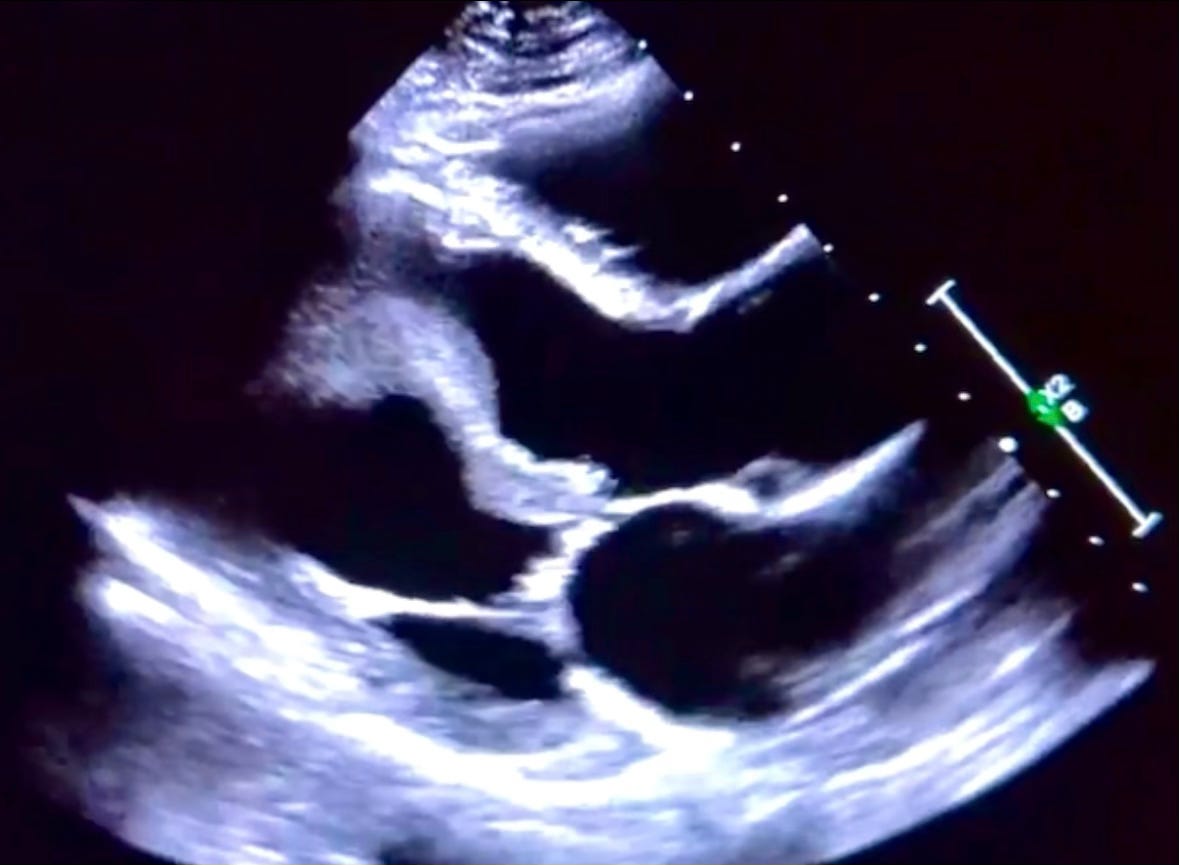

Large Snake-Like Thrombus

Something You Have Never Seen

A thrombosis is a gelatinous or solidified clot that can form within the blood vessels or inside of the heart. They tend to favor areas of stagnant flow or damaged endothelium.

These structures may obstruct circulation or embolize to other areas of the body such as the lungs (pulmonary embolism), brain (stroke), or lower extremities (artery or vein). Echocardiography is often utilized to rule out a cardiac source of emboli as the clinical team investigates its origin.

The formation of apical ventricular thrombi is commonly seen following acute myocardial infarctions as damaged tissue is exposed to the blood; fibrin, red blood cells, and platelets coagulate in the area of stagnant flow as a result. Multiple images below explore this large pedunculated thrombus and its mobile nature within the left ventricular outflow tract.